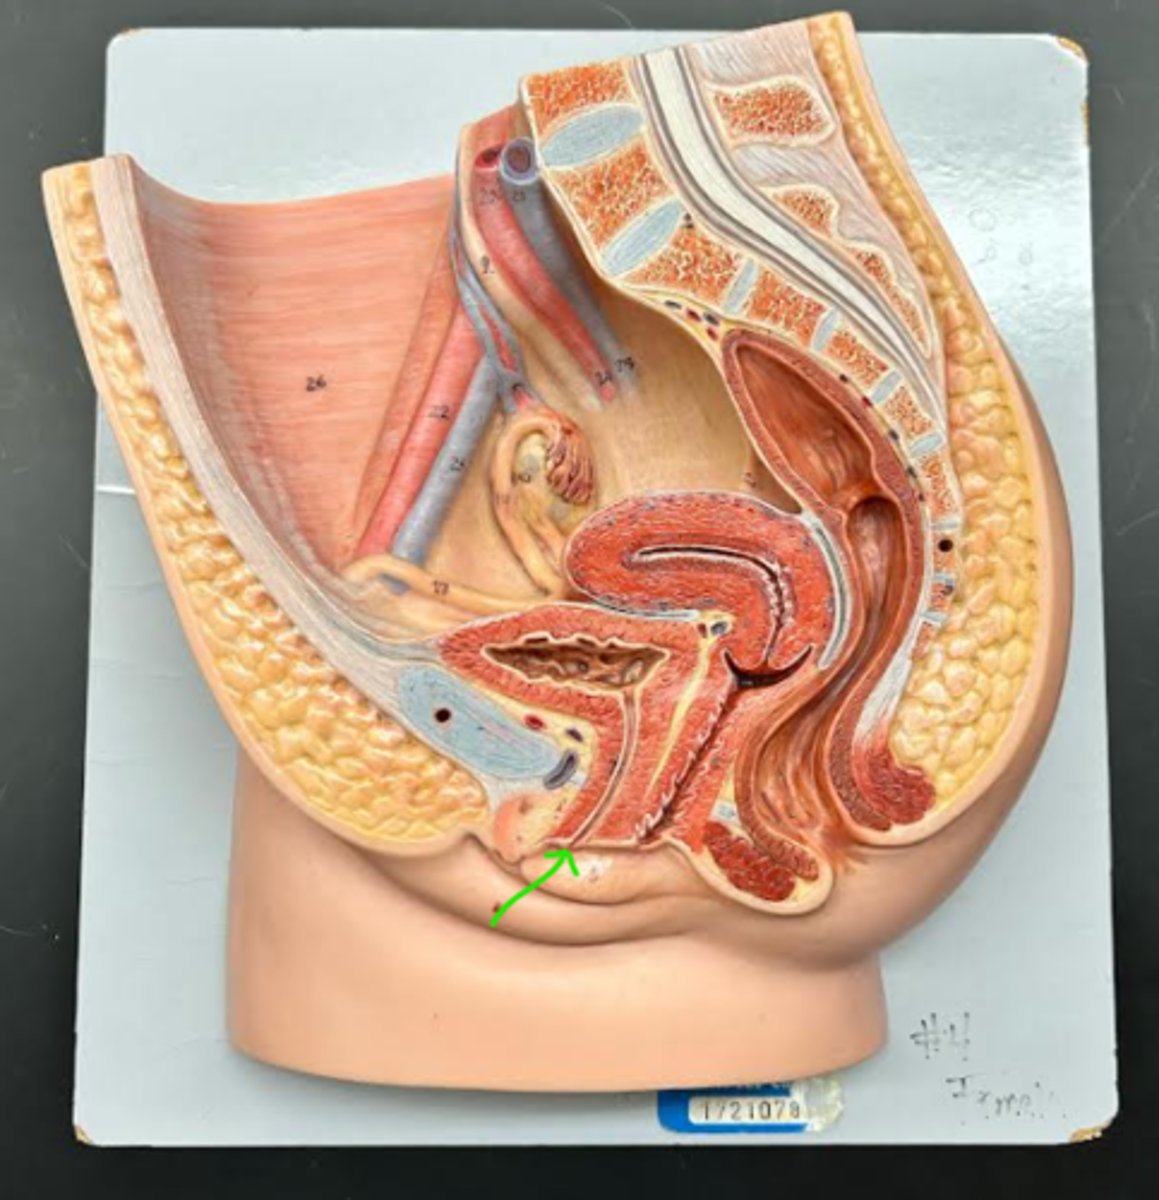

Chapter 29 Anat Phys: Female Reproductive System

Vagina

Vaginal orifice

Hymen

Vaginal fornix

Ovary

Fallopian tube

Fimbriae

Infundibulum

Ampulla

Isthmus

Uterus

Perimetrium

Myometrium

Endometrium

Fundus

Body of uterus

Cervix

Internal os

Cervical canal

External os

Labia majora

Labia minora

Prepuce

Vestibule

Clitoris

External urethral orifice